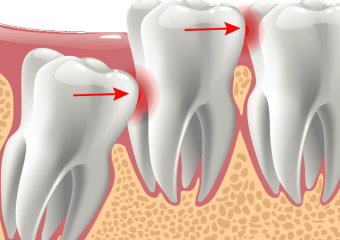

- جراحی دندان در اصفهان

مراقبت بعد از جراحی دندان عقل

مراقبت بعد از جراحی دندان عقل

در این مطلب از سایت دکتر ندا مکانیک متخصص ایمپلنت اصفهان قصد داریم نکاتی راجب مراقبت بعد از جراحی دندان عقل خدمت شما ارائه کنیم. با ما همراه باشید.